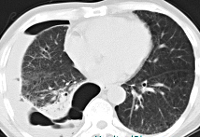

Диагноз устанавливается на основании анамнеза, жалоб, результатов объективного осмотра, инструментальных и лабораторных исследований. У больных с рецидивом рака легкого после резекции достаточно информативной оказывается стандартная рентгенография грудной клетки. Более плотное новообразование хорошо дифференцируется на фоне наполненной воздухом прозрачной легочной ткани в виде тени, расположенной неподалеку от ложа опухоли. После пневмонэктомии рентгенография неэффективна из-за тотального затемнения в области удаленного легкого.

Более информативным методом диагностики является КТ органов грудной клетки. Методика позволяет выявлять рецидив рака легкого после любых оперативных вмешательств, оценивать их размер, форму, структуру и распространенность. Кроме того, КТ дает возможность предварительно оценить состояние лимфатических узлов средостения и корня легкого. Точная оценка состояния лимфоузлов при рецидиве рака легкого осуществляется на основании данных МРТ грудной клетки. При наличии лимфогенных метастазов определяются конгломераты с неровными контурами, дающие сигнал высокой или средней интенсивности.